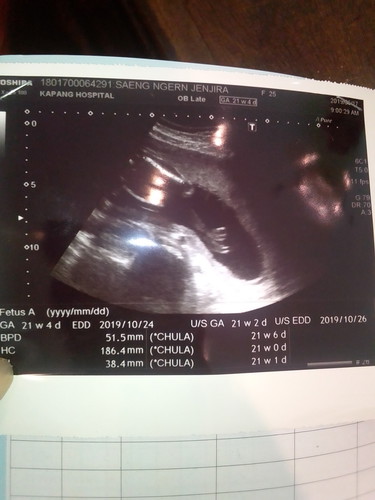

รูปผลซาว

แบบนี้ ญ ช คะ. แม่ๆบ้านไหนดูเป็นบ้าง

น่าจะ ชายคะ น่าสังเกตุตรงลูกศรชี้ เหมือนเค้าชี้ให้เห็นปิกาจูคะ

ใบทค่หมอให้มา ตรง Genitalia normal MหรือF ค่ะ M ชาย F หญิง ค่ะ

รูปที่ลงมาคือช่วงไหนของตัวคะ ดูไม่ออกเลย